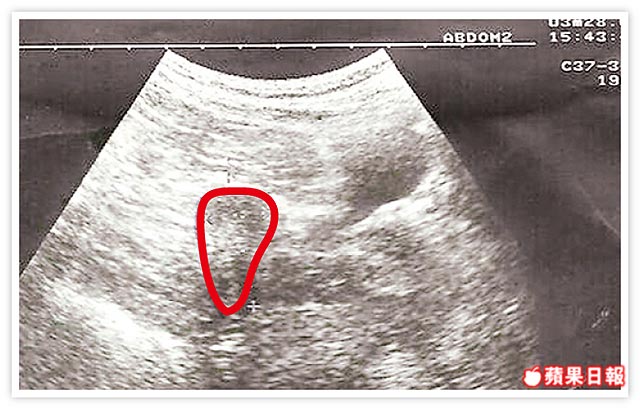

嚴重的卵巢過度刺激症候群: 7 年不孕 , 多囊性卵巢症候群 ...2013.09.03

她不孕症1.年紀32歲 2.做人工授精五次失敗 3.不孕症七年  ...2013.09.03